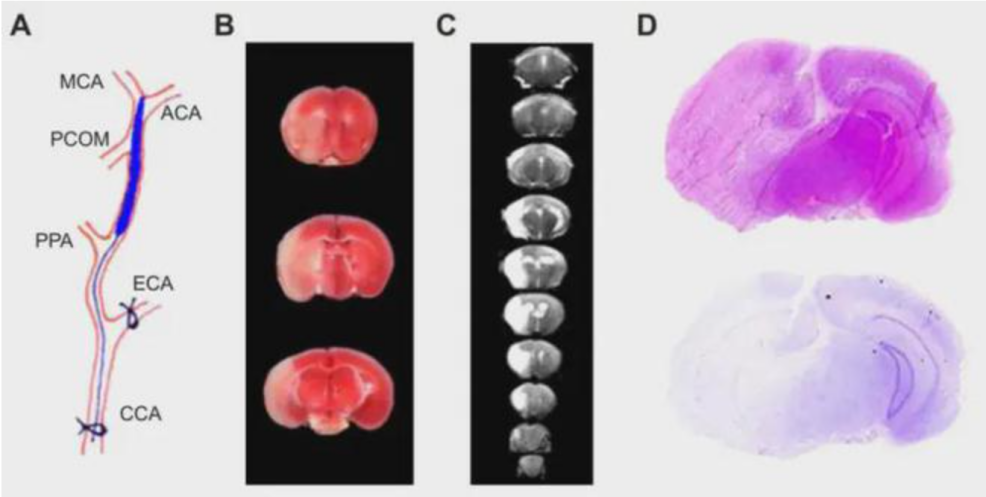

阻塞大脑中动脉(MCA)及其分支的技术最接近该疾病临床病理表现,大脑中动脉是其在人类缺血性中风中最常受到影响的大脑血管。在闭塞性MCA中风模型中,使用最广泛的模型通过短暂或永久性大脑中动脉栓塞(MCAO)在顶叶皮层和纹状体中产生局灶性病变。MCAO模型的诱导包括暂时闭塞颈总动脉(CCA),将缝合线引入颈内动脉(ICA)或经横断的颈外动脉(ECA),并收紧缝合线直到其中断向MCA的血液供应。

MCAO是Middle Cerebral Artery Occlusion的缩写形式,中文意思为中脑动脉栓塞。大脑中动脉栓塞模型并不是把线栓插进大脑中动脉,而是经颈内动脉入颅并插入大脑前动脉,从而阻塞来自栓塞侧的大脑前动脉的血供,以及堵塞接受后交通动脉血供的的颈内动脉颅内段。本课题采用线栓法,线栓法具有不开颅、效果肯定、可准确控制缺血及再灌注时间的优点。

MCAO模型病理学检测示意图

MCAO模型造模成功后,灌流取材的脑组织出现明显的单侧萎缩,缺血等形态学变化,通过HE染色可以检测MCAO模型中脑区域的形态变化。

图3 大鼠MCAO造模后脑组织形态变化示意图